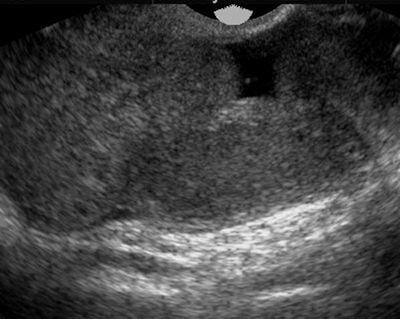

| Although not a typical acute gynecological presentation, this patient presented with abdominal distension, nausea, and vomiting. This transvaginal ultrasound demonstrated symmetric enlargement of the left ovary; however, both ovaries were similar in appearance (often they can be more than 12 cm in size) with multiple cysts of varying sizes. Ovarian hyperstimulation syndrome can also be present with ascites and pleural effusion. Pericardial effusion (due to capillary leak) can also be present. |